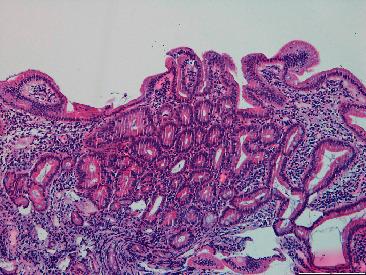

Gardner's syndrome is an autosomal dominant disease caused by a mutation in the gene with 20-30% of cases presenting de novo. This entity is a variant of familial adenomatous polyposis, with a prevalence of 3/100,000 habitants. It may present as early as 2 months of age with a variety of both colonic and extracolonic symptoms. We report a case of a 21-year-old man, without any known family history, presenting with microcytic hypochromic anemia and constitutional symptoms for two months. Ultimately, after the etiological study, Gardner syndrome diagnosis was established as an index primary familiar case. Gardner syndrome is a clinical challenge which requires a prompt suspicion in order to reach its diagnosis. Given the malignant evolution of adenomas in 100% of untreated patients, early identification of extraintestinal manifestations (identifiable prior to colonic symptoms) is of the essence. A consequent endoscopic study to confirm gastrointestinal involvement is essential for a more favorable prognosis.

加德纳综合征是一种常染色体显性疾病,由该基因的突变引起,20%至30%的病例为新发。该病症是家族性腺瘤性息肉病的一种变体,发病率为十万分之三。它最早可在2个月大时出现,伴有多种结肠和结肠外症状。我们报告一例21岁男性病例,无任何已知家族病史,出现小细胞低色素性贫血和全身症状达两个月。最终,经过病因学研究,加德纳综合征被诊断为原发性家族性病例。加德纳综合征是一项临床挑战,需要迅速怀疑以便做出诊断。鉴于100%未经治疗的患者腺瘤会发生恶性演变,早期识别肠外表现(在结肠症状出现之前即可识别)至关重要。因此,进行内镜检查以确认胃肠道受累对于获得更良好的预后至关重要。